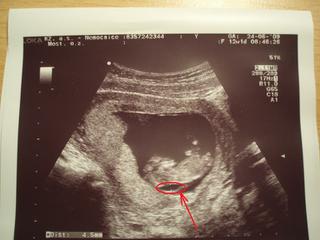

kto vie ake su normalne NT hodnoty (meranie hrubky sije ultrazvukom) v 13 - 14?

Ahojte, práve mi prišli výsledky z prvotrimestrálneho skríningu a hoci výsledky sonografie dopadli podla dokiho dobre, NT=1,7, tak podla veku (39) a biochemie krvi mam pozitivny skrining na Downom syndrom 1:213 ☹ , mali ste niektora takyto vysledok a napriek tomu zdrave babo?

NT mas peknu hodnotu. asi ta kvoli veku odporucia na amnio, ale skutocne vzhladom k veku to mas riziko velmi dobre

Ahoj, já měla 1,9 mm a riziko DS 1:220, přestomi doporučili amniocentézu, kterou jsem podstoupila před týdnem, teď čekám. Mám to prý brát jako zajišťovací úkon, aby si byli zcela jistí 🙂.

před nedávnem jsem tu řešila váš problém s NT hodnotami měla jsem 3,2 a riziko na DS 1:7 mám už půl roku zdravou krásnou holčičku a tak iVám tady přeju zdravé a krásné dětičky !